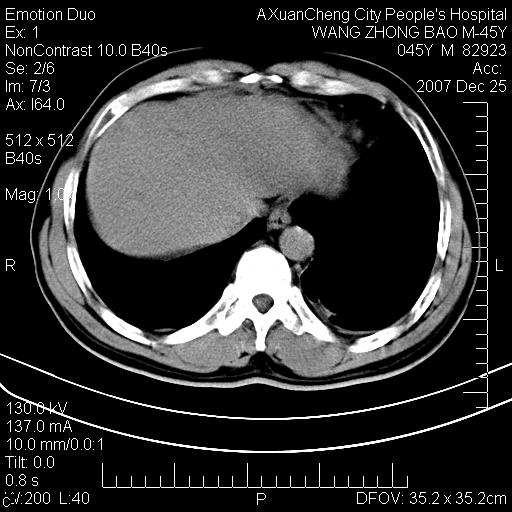

以下是引用qiuleiyu在2007-12-25 18:14:00的发言:[br]胰腺增大,周边渗出改变,肾前筋膜明显增厚,示少量积液.胆囊壁毛糙,周边少许渗出,胆总管壁厚,异常强化,然扩张不明显.结合病程急短;考虑;胆管炎,胆囊炎,胆源性胰腺炎可能大,请结合实验室检查及随访.

以下是引用lisihao在2007-12-25 14:23:00的发言:[br]急性水肿型胰腺炎[br]依据:1、胰腺弥漫性肿大,边缘稍毛糙;[br] 2、双侧肾周筋膜增厚,尤以左侧为甚(重要征象)[br] 3、双侧后胸膜增厚(刺激性炎症);[br] 4、结合病史,查血尿淀粉酶应该可以确诊。